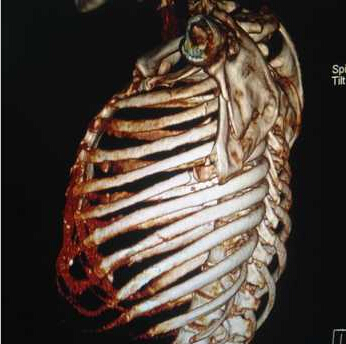

患者,35岁,女性。多处创伤,大家能看出哪些地方骨折了吗?